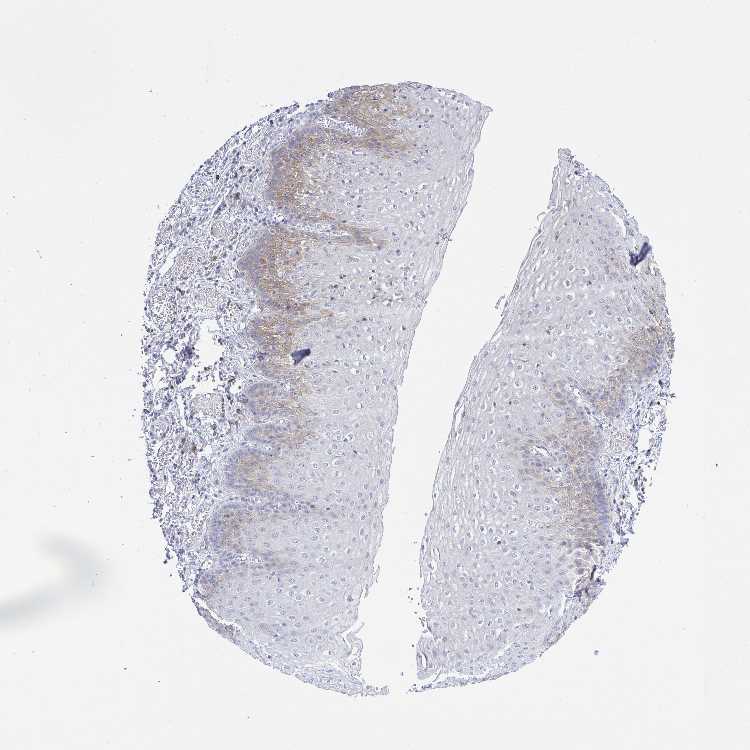

ESOPHAGUS - Antibody stainingi

Antibody staining in the annotated cell types in the current human tissue is reported as not detected, low, medium, or high, based on conventional immunohistochemistry profiling in selected tissues. This score is based on the combination of the staining intensity and fraction of stained cells.

Each image is clickable and will lead to virtual microscopy that enables deeper exploration of all samples and also displays staining intensity scores, fraction scores and subcellular localization as well as patient and tissue information for each sample.

Antibody HPA017285

Squamous epithelial cells Low